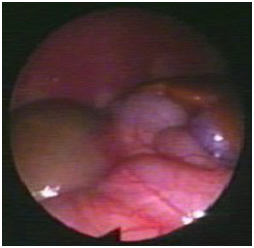

We report the case of a 28 days old girl with an antenatal diagnosis of abdominal mass. The physical examination was negative, blood sample results were within normal ranges (alpha-fetoprotein, bHCG and CA125). Urinalysis showed a small amounts of blood cells and leucocyturia, whereas the urine culture was positive for Escherichia coli (105). A micturitional cystourethrography and a complete abdominal ultrasound were performed. The micturitional cystourethrography showed a normal bladder for size and localization, with a lateral deflection of bladder imaging due to mass compression (Figure 1). The abdominal sonography showed a roundish mass with linear and exogenous margins, located in an anteromedian position compared to both the lower pole of the right kidney and the sub hepatic region. The mass was about 4x3x3 cm, and had a mixed solid -liquid echo structure (Figure 2) (Figure 3). A CT scan confirmed the presence of a 4cm cystic formation in the hepatic region but a subsequent MRI showed the mass in the right iliac fossa, and ruled out the involvement of other organs. In order to define a correct diagnosis and the subsequent surgical strategy we decided to perform a laparoscopic exploration. It was possible to identify a cystic mass in the sub-hepatic space with a diameter of 3-5cm. The mass was mobile, well delimited by the surrounding organs, with a thin long vascular pedicle (Figure 4). The exploration of the abdomen was normal and the left sided ovary and fallopian tube were normal. Although the diagnostic tests were negative, to completely rule out a neoplastic formation, the mass was totally removed through a minimal laparotomy to avoid dissemination of the fluid within the abdominal cavity in case of cyst rupture, according to the uncertain nature of che cyst. The histological diagnosis was “self amputated ovarian cyst” with necrosis and hemorrhagic fluid inside. The postoperative period was regular and the patient discharged on the second day after surgery.

Figure 2 Ultrasonography: A roundish mass with linear and exogenous margins, about 4x3x3 cm with a mixed solid -liquid echo structure.